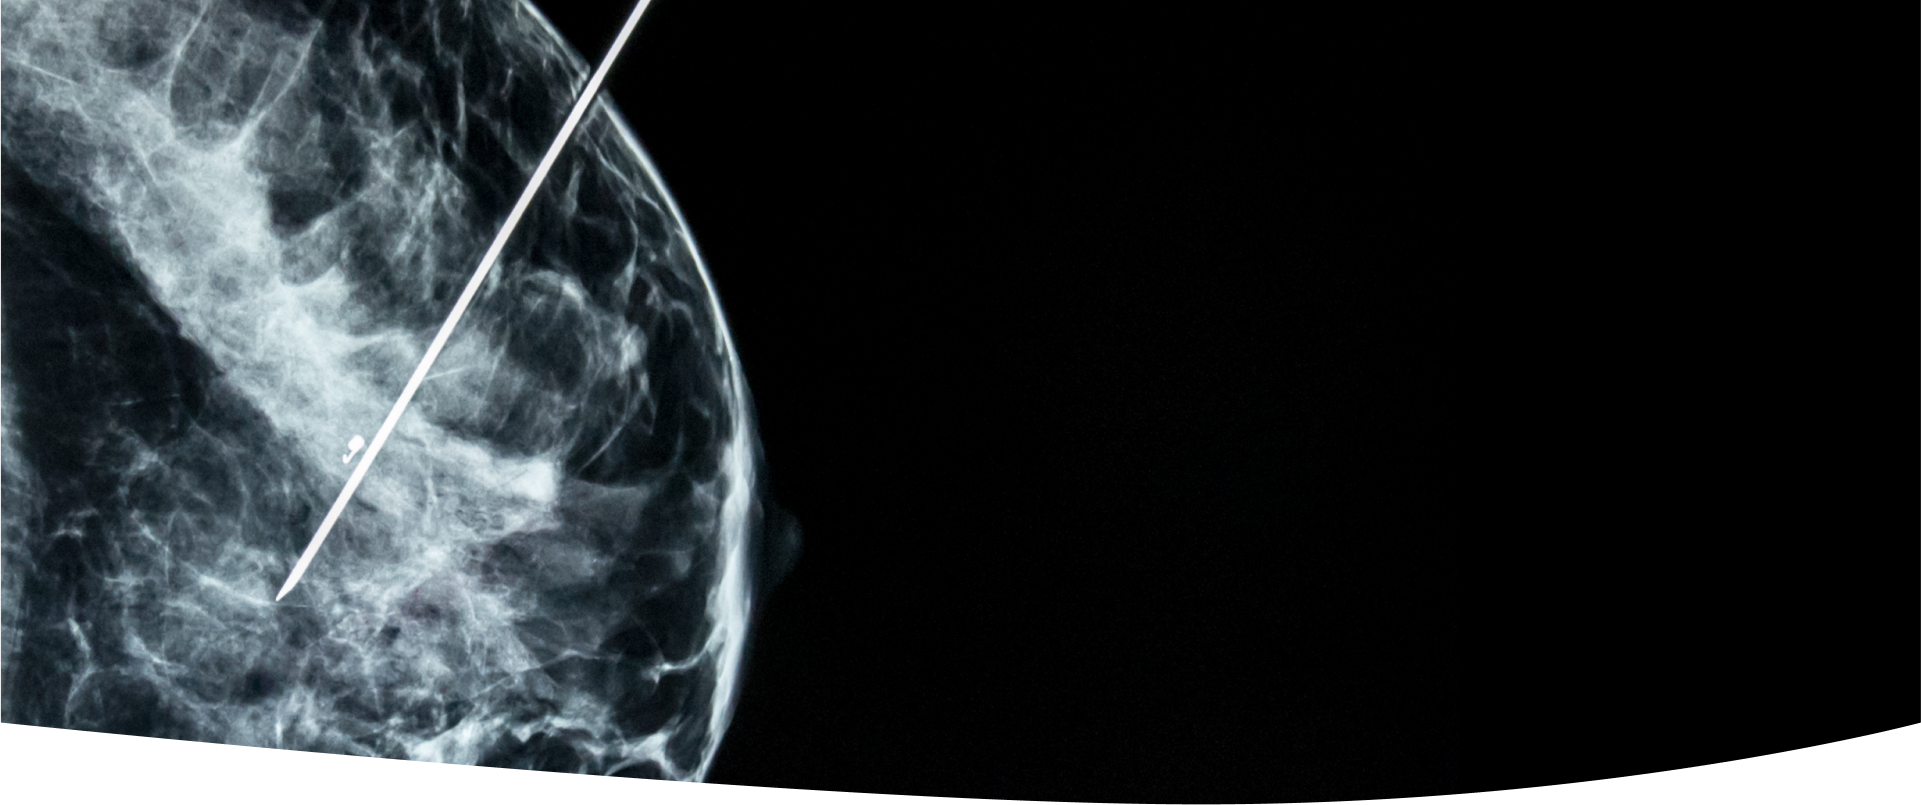

Radiologie și imagistică medicală